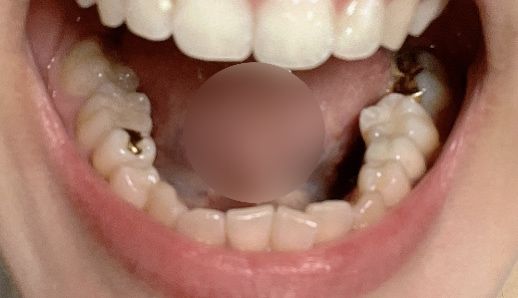

사진3 . 아랫니 아치

• 3번 째 사진